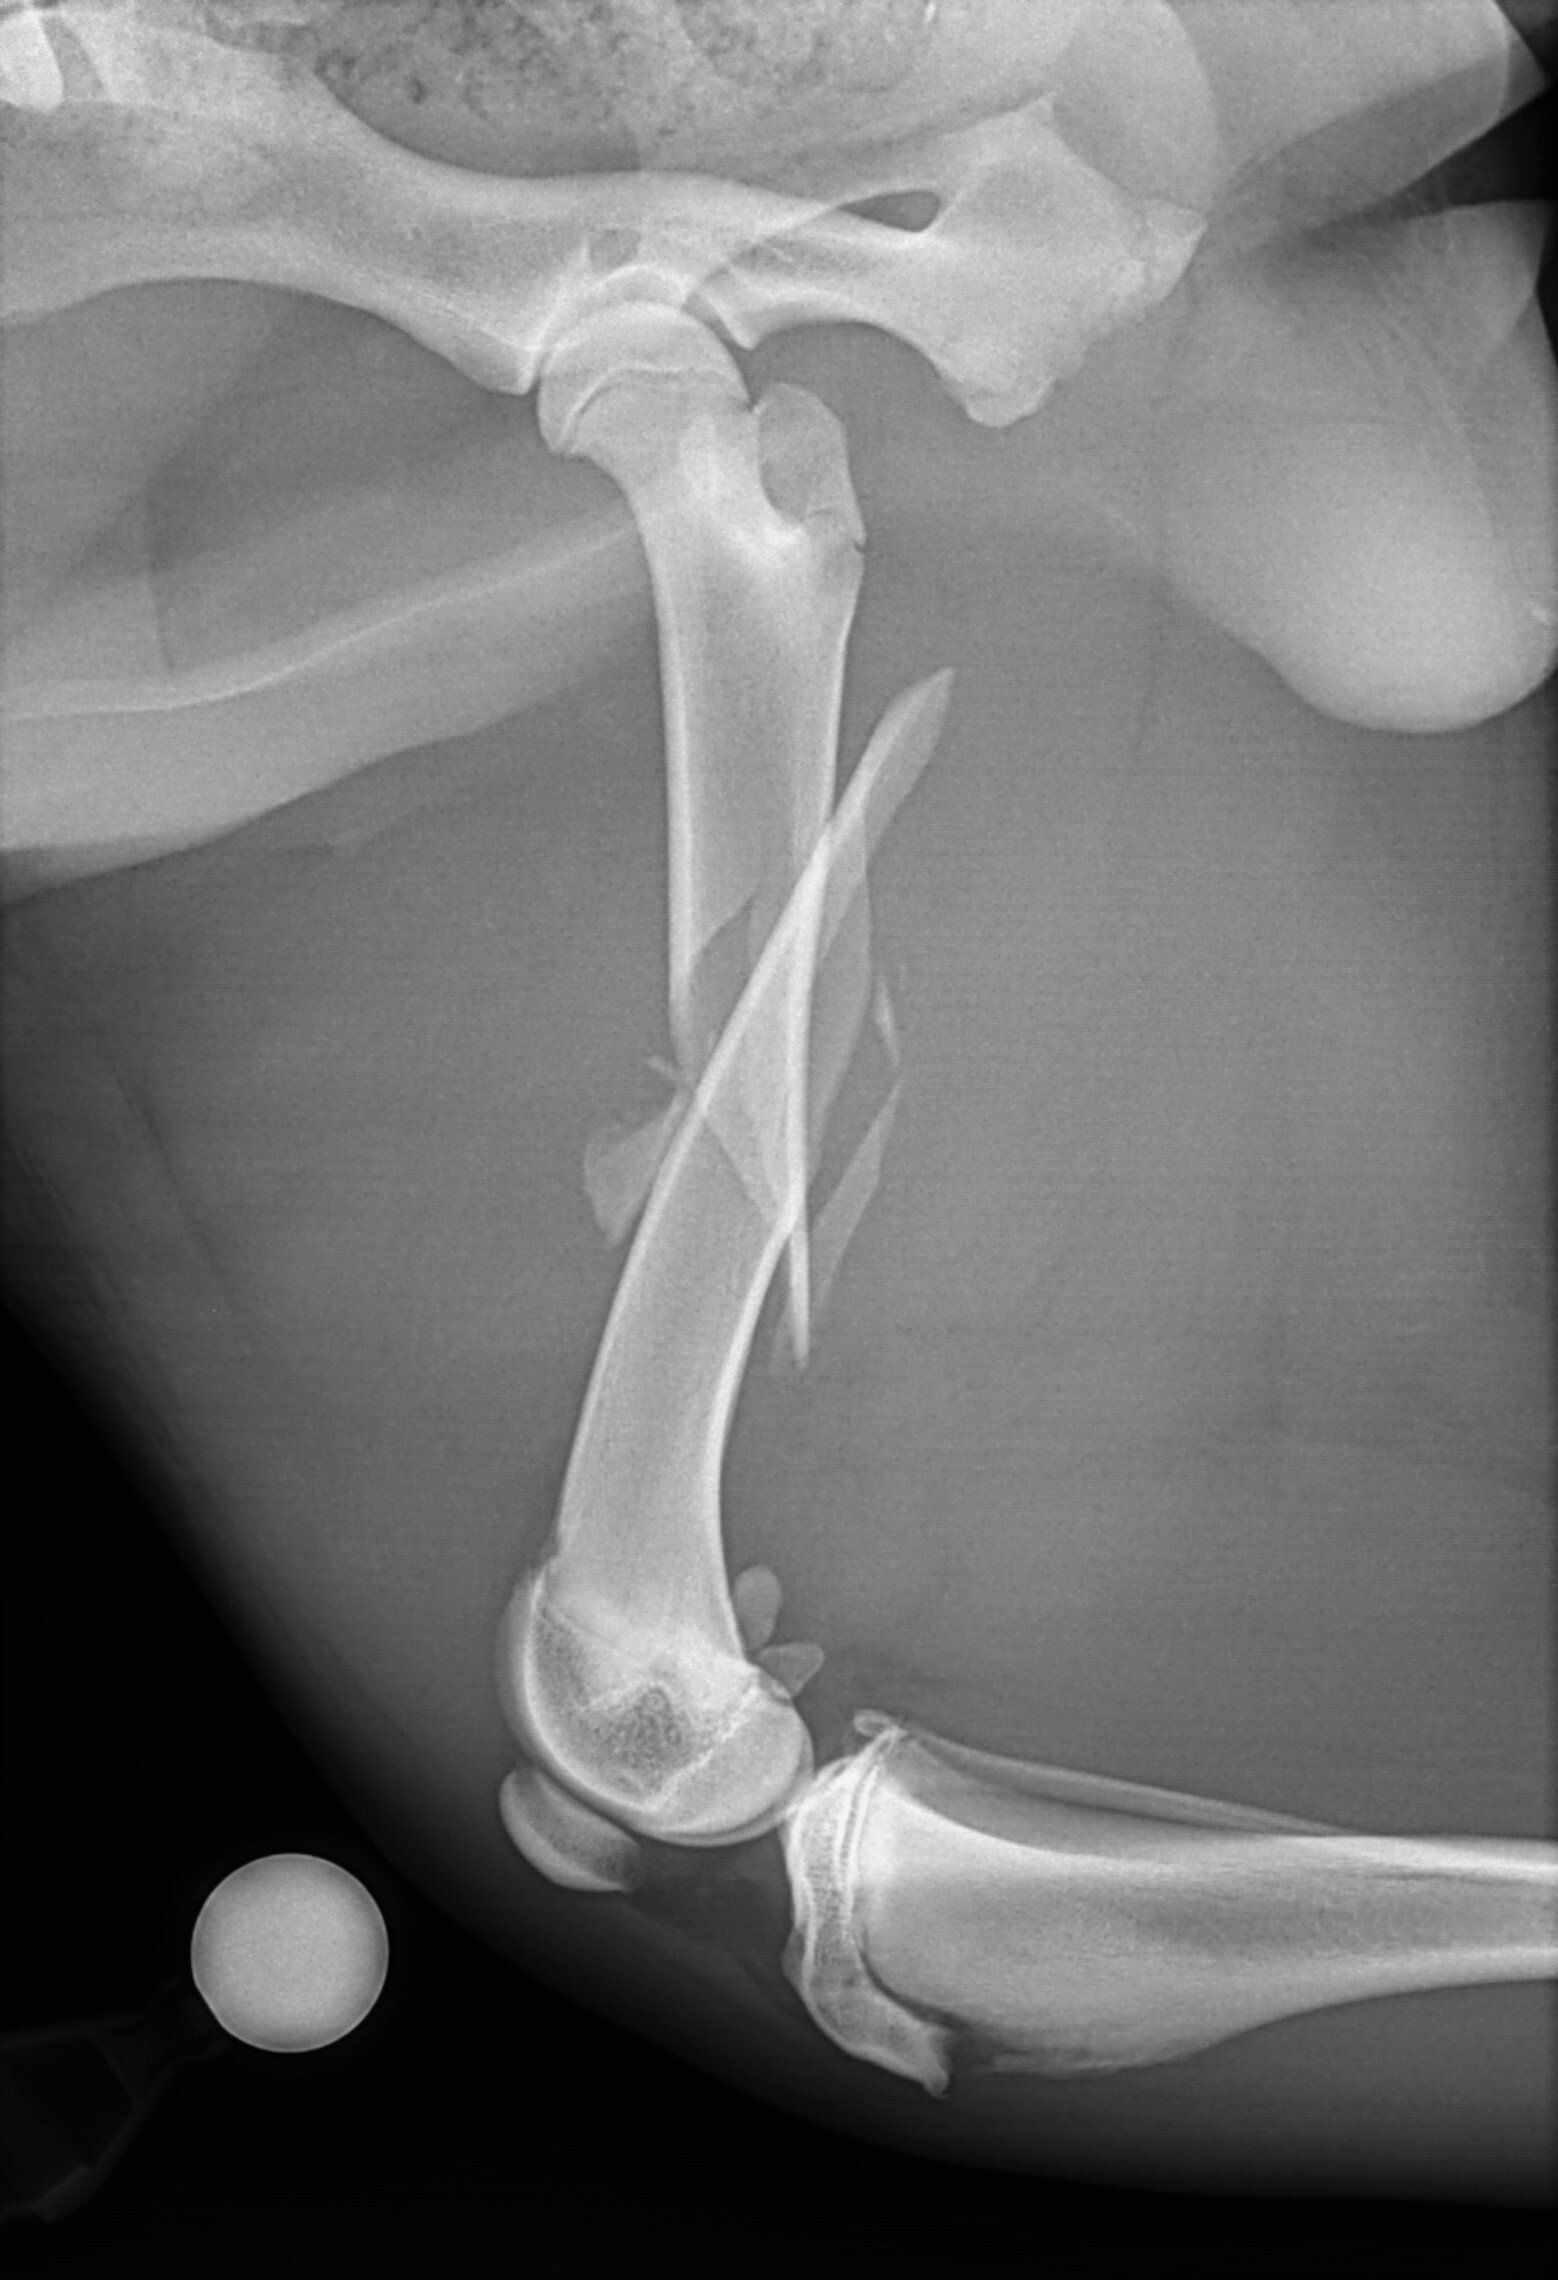

Leg fractures are one of the most common orthopedic problems presented at our clinic and usually result from a traumatic mishap. They can be treated in a variety of ways depending on the location and type of fracture. We can apply a cast to treat certain fractures; however, many fractures will require surgical intervention:

- “Pinning” stabilizes the fracture by inserting a long stainless steel rod into the middle of the bone across the fractured area.

- “Plating” involves attaching a flat stainless steel plate to the bone using screws on either side of the fracture.

Below are x-rays of just a few orthopedic surgeries before and after that Dr. Gose has performed.